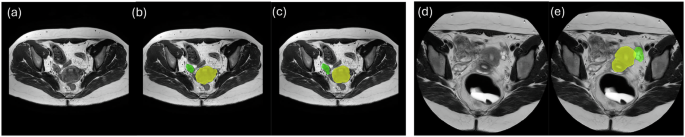

This is a retrospective study. Our dataset comprises multi-sequence MRI scans collected from two clinical institutions in Texas: The Memorial Hermann Hospital System and Texas Children’s Hospital Pavilion for Women. Although both datasets were from patients suspected of having endometriosis, they include different MRI sequences obtained using varying protocols and MRI scanners. The study and data sharing policy allowing sharing for research purposes was approved by the Committee for the Protection of Human Subjects at UTHealth (protocol no HSC-SBMI-22-0184), which includes requirements for patient informed consent. Figure 1 shows examples of MRI scans and the corresponding labels for two Datasets.

Both datasets are de-identified by converting DICOM files to NIfTI format. The labels were manually contoured based on different MRI sequences by different raters in 3DSlicer. For the first dataset, three raters manually contoured structure segmentations for the uterus, ovaries, and endometriomas. The uterus and ovaries were contoured prioritizing based on T2-weighted sequences, while endometriomas were contoured prioritizing T1-weighted fat suppressed sequences. Note that in all cases, both T1 and T2 sequences were used. An experienced abdominal radiologist proposed a segmentation contouring guideline and reviewed the final labels from different raters to make necessary corrections. Manual segmentations from different raters are used to analyze interrater agreement. Each subject had one to two MRI sequences with two to four labels when the structures were present. Among the 51 subjects in Dataset 1, 11 (22%) were annotated by three raters, 22 (43%) by two raters, and 18 (35%) by one rater. For the second dataset, the uterus, ovaries, cysts, and endometriomas were manually contoured by an obstetrician-gynecologist assistant supervised by an expert Gynecologist, with all structures contoured based on T2-weighted fat suppression MRI with the same protocol. Although all patients in this dataset were diagnosed with endometriosis, only 12 had endometriomas.